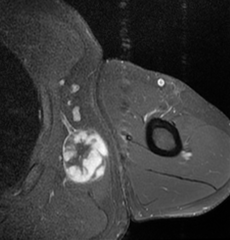

-

MRI of myxoid liposarcoma of high grade, in left axillary region of 40 year old man. Highlighted by the white color. Horizontal section.